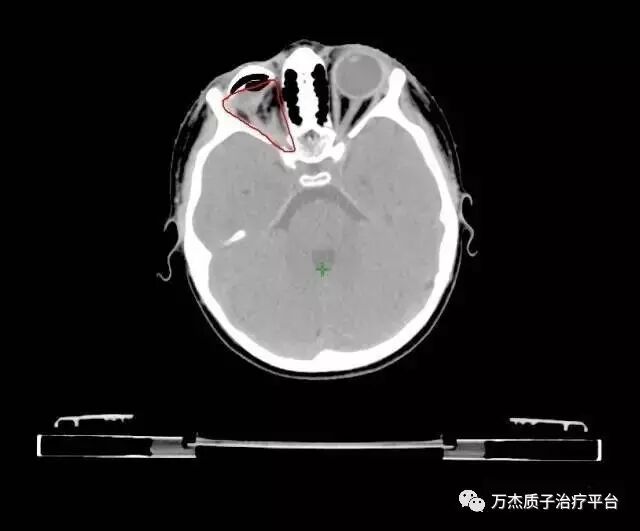

病情:右侧视神经上皮细胞瘤10月余。于2008年3月眼科检查发现右侧视神经萎缩,2008年4月14日查头颅MRI示:右侧眼球后占位。于2008年8月19日手术活检病理为:视神经上皮细胞瘤。2008年12月2日----2009年3月16日行3个周期化疗(HIT-SKK.2000)第一周期化疗后复查CT病灶有轻微改善,第二周期后复查肿瘤进展。于2009年3月26日行外科手术眼球摘除术,肿瘤切除病理视神经上皮细胞瘤,术后置一假体。术后于2009年4月20日—2009年9月11日行4周期化疗(HIT-2000)于2009年7月14日复查:残留灶缩小。2009年11月17日PET示:病灶区FDG摄取活跃,考虑残留区病灶进展。为行质子治疗来我院。入院时间2010年2月9日。入院后行质子治疗剂量DT60CGE/30F/35d

治疗前图像:

质子治疗剂量分布:对侧眼睛、视神经及脑组织均受到良好保护;

俄罗斯3岁小患者五年随访复查,未见复发迹象。